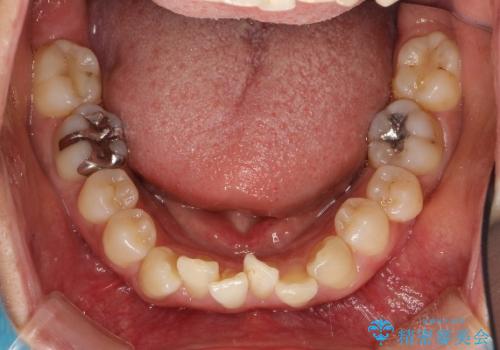

- 上下の歯並びにガタつきがあり、また、上下前歯の前後のズレが大きく上の前歯が突出しています。

インビザラインではガタつき(叢生)の改善だけでなく、上下の前後的なズレについてもアプローチが可能です。

インビザラインの特色を生かした歯牙移動計画を作成し、非抜歯にて治療を行いました。